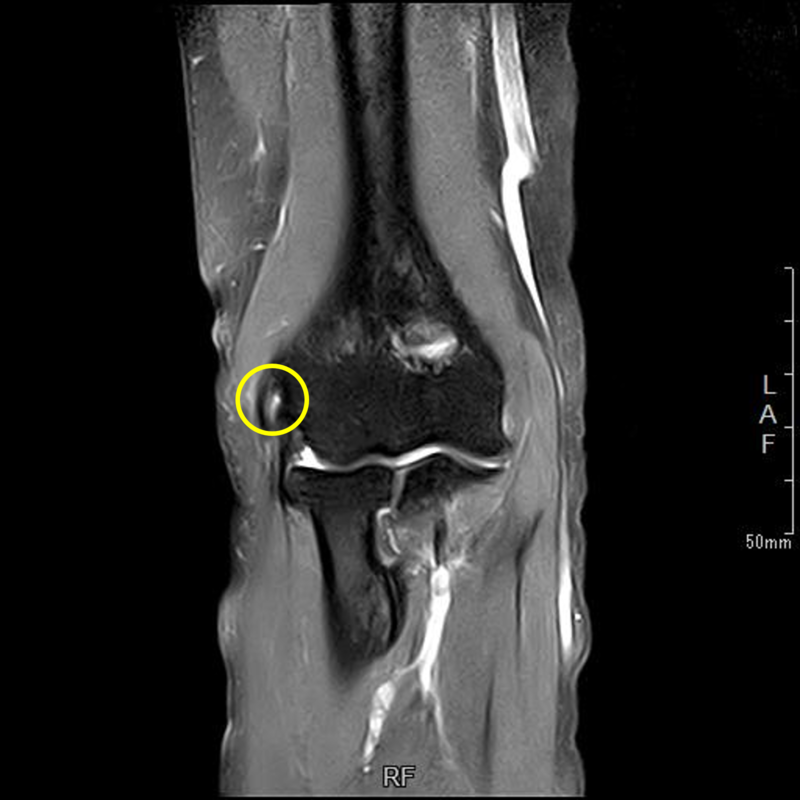

肘離断性骨軟骨炎(野球肘外側型)

肘の離断性骨軟骨炎(以下:OCD:osteochondritis dissecans)は上腕骨小頭という部位に好発することが多いです。

OCDは成長期の代表的なスポーツ障害であり、野球などといった投球・投擲動作を行うスポーツ選手で投球側に発生することが多いです。大半は10-12歳で発症し成長期における有病率は2-3%と頻度は少ないが進行するとスポーツにみならず、日常生活お支障をきたすことが多い怪我です。そのため、早期発見・早期治療が重要となります。

OCDを発見するにはレントゲンや超音波検査で上腕骨小頭軟骨下骨の状態を観察します。

軟骨下骨の不整像が軽微か不明の場合はMRI検査を行いOCDの確定診断を行います。

症例提示

12歳・男性・スポーツは野球(週2回/4年間)

2024年3月頃から外傷誘因なく疼痛出現。

2024年4月上旬、他院受診して超音波検査で軟骨が剝がれていると診断を受けたが経過観察のみ。

2024年5月、当院受診。レントゲン撮影をして離断性骨軟骨炎と診断されてリハビリ開始。

リハビリでは、徒手療法(マッサージ)・運動療法(筋力トレーニング ストレッチ)・物理療法を実施していましたが、

疼痛消失には至らず、組織修復を目的に体外衝撃波を実施しました。

体外衝撃波(拡散型圧力波治療)は、週1回の頻度で3回実施しました。

現在は、リハビリテーションでトレーニング継続中です。